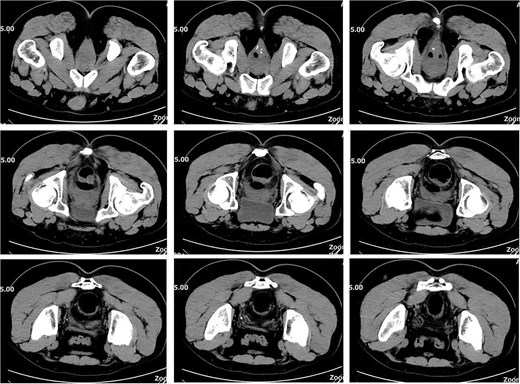

On postoperative Day 21, a follow-up pelvic CT scan indicated local gas accumulation around the rectum, suggesting an absorption phase of the infection (Fig. 4). By postoperative Day 28, a pelvic CT scan demonstrated minor gas accumulation at the anterior edge of the rectosigmoid junction, consistent with infection resolution and gas absorption in the surrounding area (Fig. 5). By postoperative Day 49, a pelvic CT scan revealed no abnormal density shadows in the perianal skin and soft tissues, with preserved fat planes (Fig. 6), indicating complete resolution of the perirectal infection and restoration of normal clinical status.